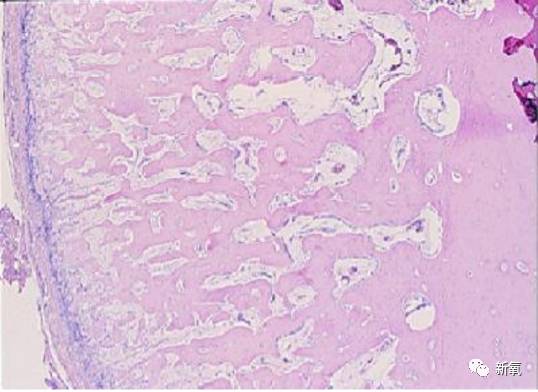

鼻骨增生实际上是骨膜增生。骨膜是附着在骨骼表面的一层结缔组织薄膜,对骨骼有营养和保护作用。骨膜增生是骨膜受到外伤或其他刺激后的一种正常的增生性反应,也是自我修复的一个重要步骤。

受刺激的骨膜细胞增殖变厚,继而骨膜下的成骨细胞增生并活跃性增加,并产生新的骨骼以修复缺损。So,你们可以想象一下,本身要推下去的骨头,这块地方又长了新的上去,是不是外观上看起来就像没效果的?

图片左侧纵向排列,细胞密集的膜性结构为骨膜,骨膜下有大量的新生骨骼组织。

早期大多采用磨骨法来进行鼻骨缩窄,结果增生概率很高,后来医生们发现鼻骨截骨法出现增生大大减少。也就是说磨骨时对骨膜损伤导致了增生的产生,如果仅仅针对鼻骨进行截骨手术,就可以最大程度避免增生。